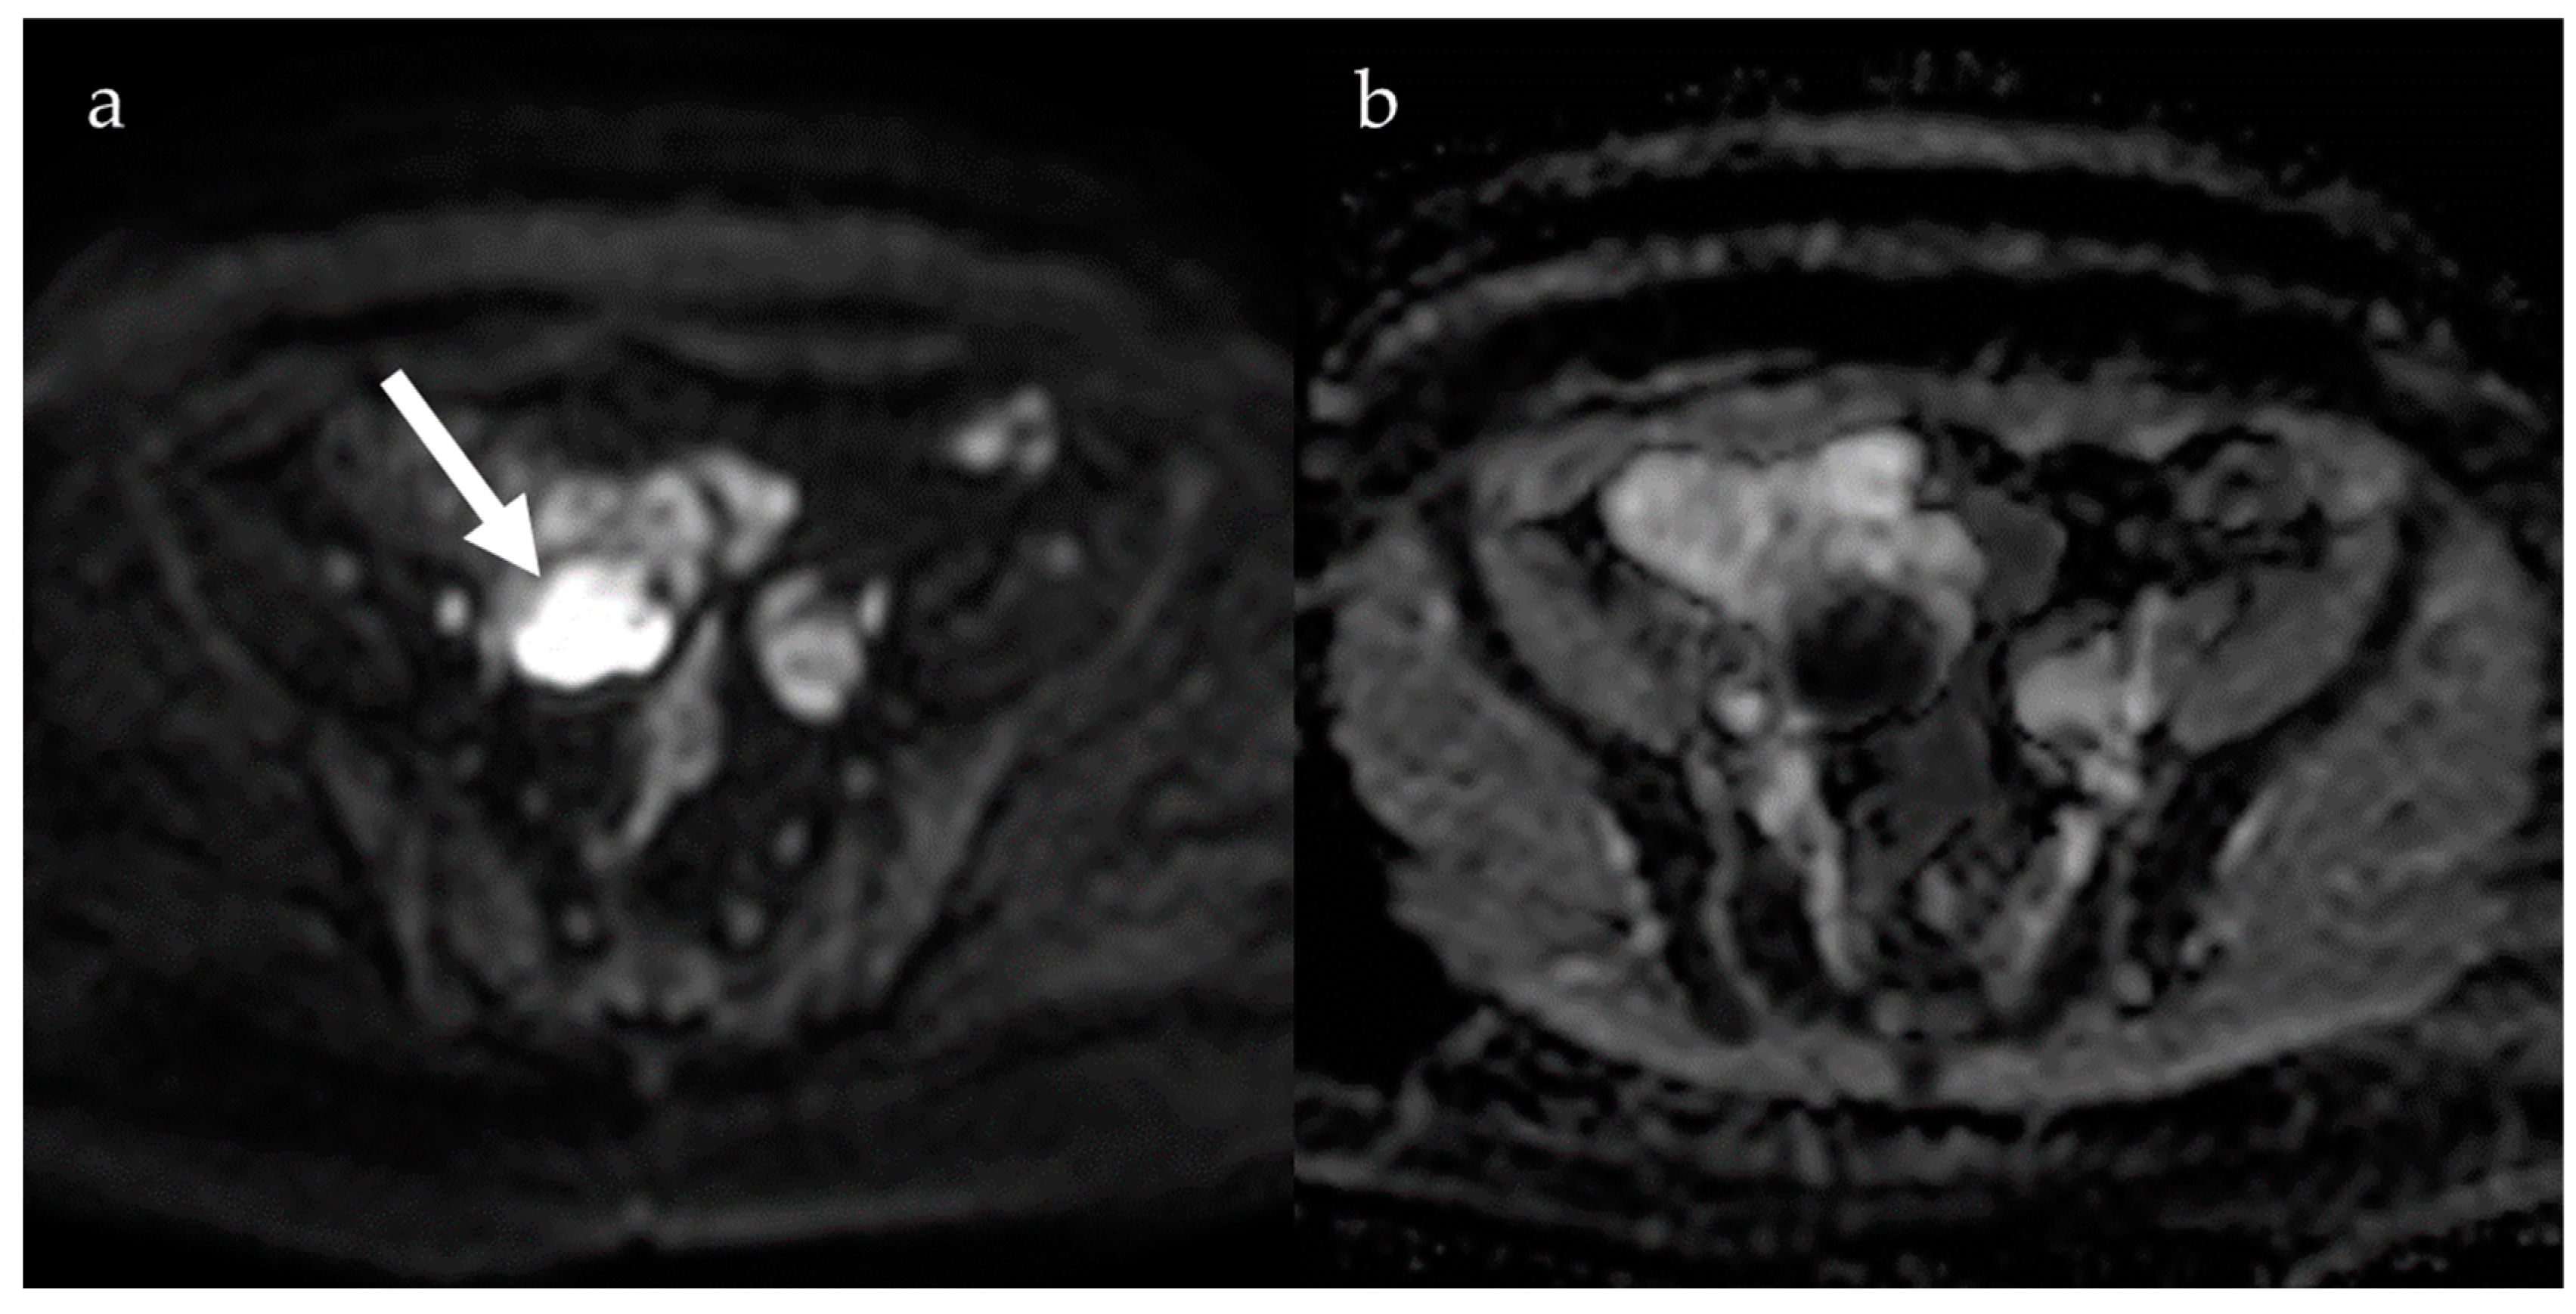

4. Diffusion-Weighted Imaging